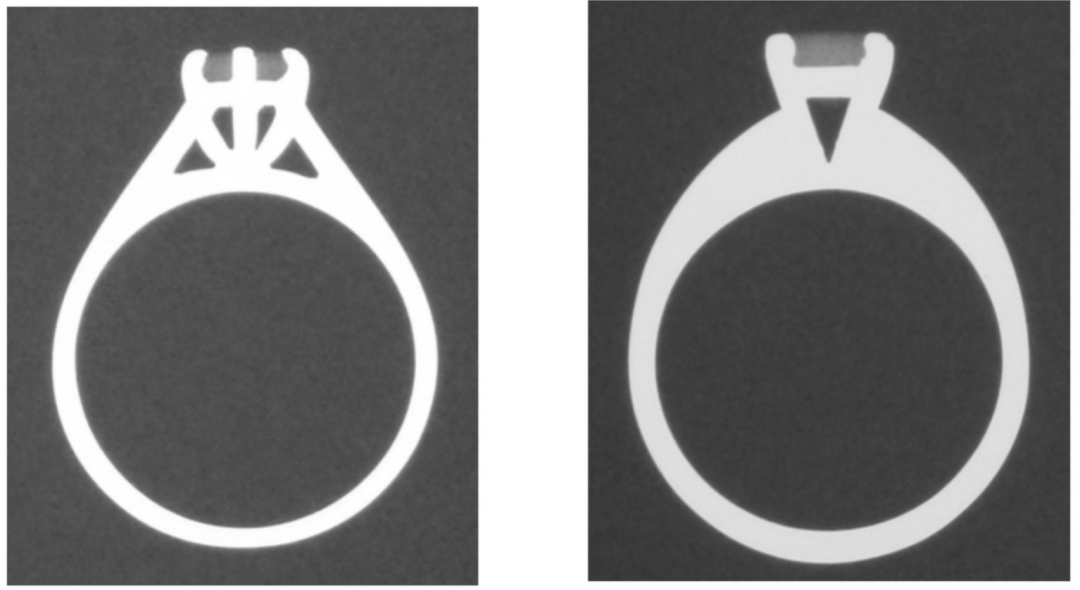

一项研究对经过认证的天然钻石戒指和立方氧化锆晶体做的“钻石”戒指在相同曝光参数下进行成像。

天然钻石戒指的X线照片如(图2)所示,而立方氧化锆晶体仿制的“钻石”戒指的射线照片如(图3)所示。

• 天然钻石始终比立方氧化锆晶体具有更高的射线可透性,表现为低密度。

• 钻石由原子序数为6的碳制构成,其密度与人体组织非常相似,而立方氧化锆的密度与戒指周围的金属一样。

图2. 2颗钻石戒指在X线下的表现